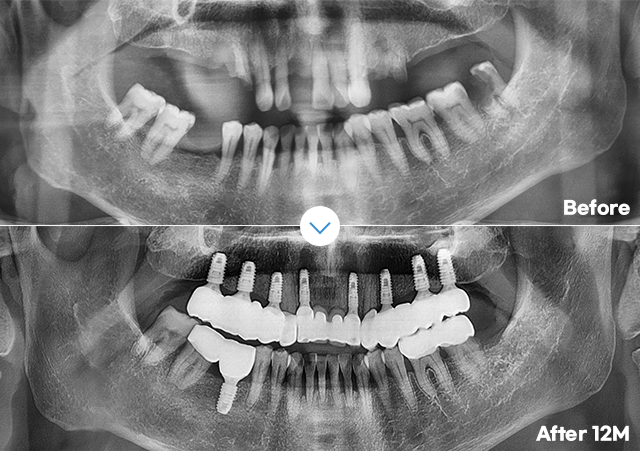

3D CT 진단 검사, 3D 컴퓨터 모의 수술 진행으로

0.1mm 오차까지 확인하여

정확하고 안전한 수술계획을 수립합니다.

오차없이 초정밀 식립 3D 데이터로 철저한 수술계획네비게이션 임플란트